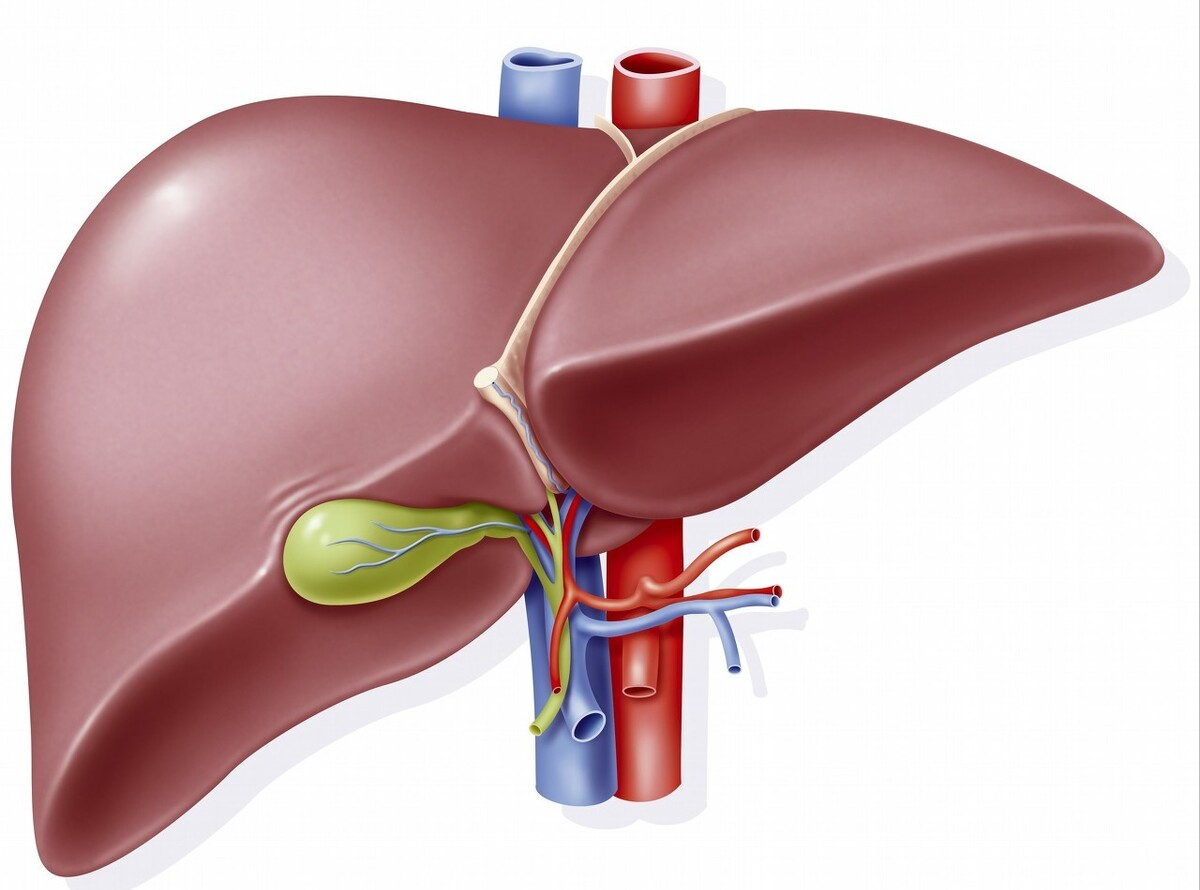

肝脏本身在体内就发挥的消化、免疫、调节激素、解毒等功能,身兼多职又异常坚强,是最强储备代偿能力的器官,受伤了也不易被察觉,即使肝细胞已经损坏70%,也未必会出现不适。